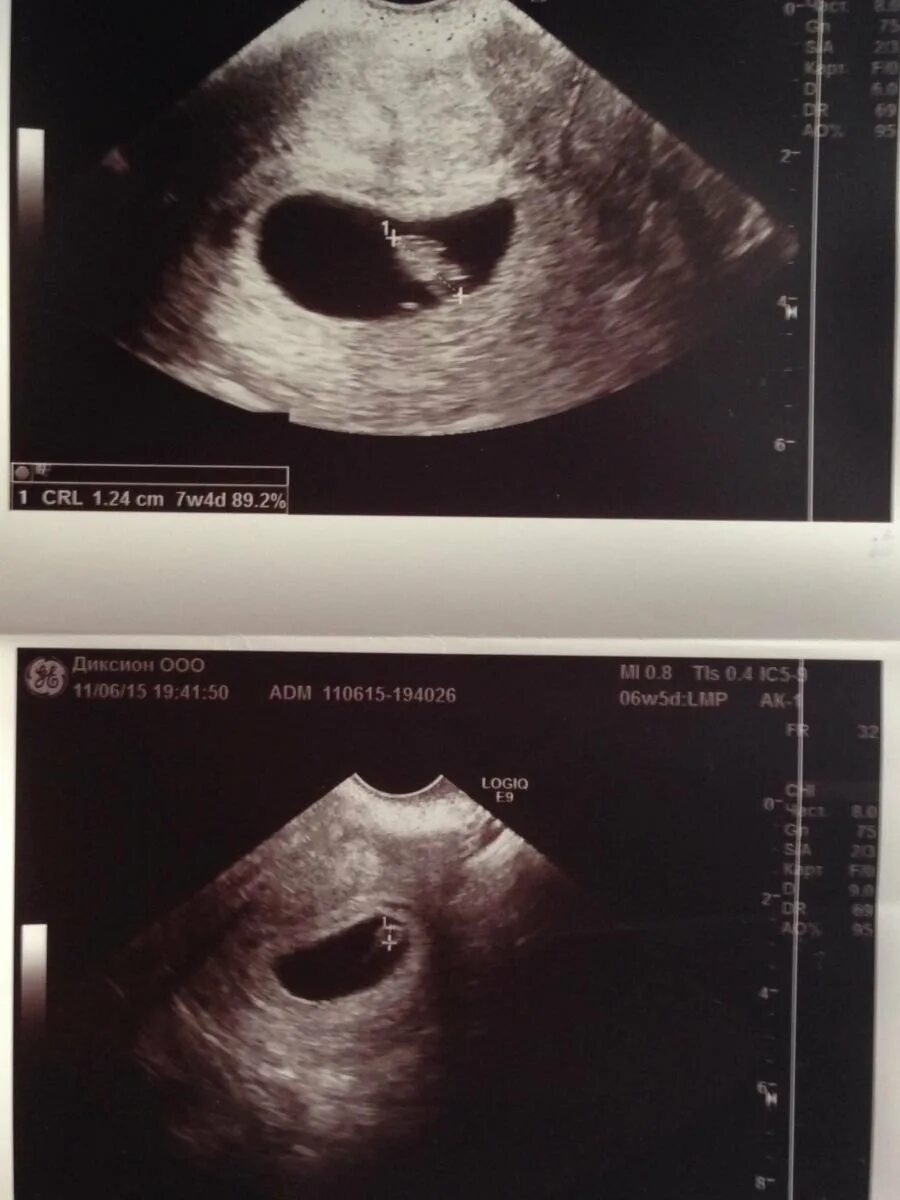

Эмбрион 7 дня форум